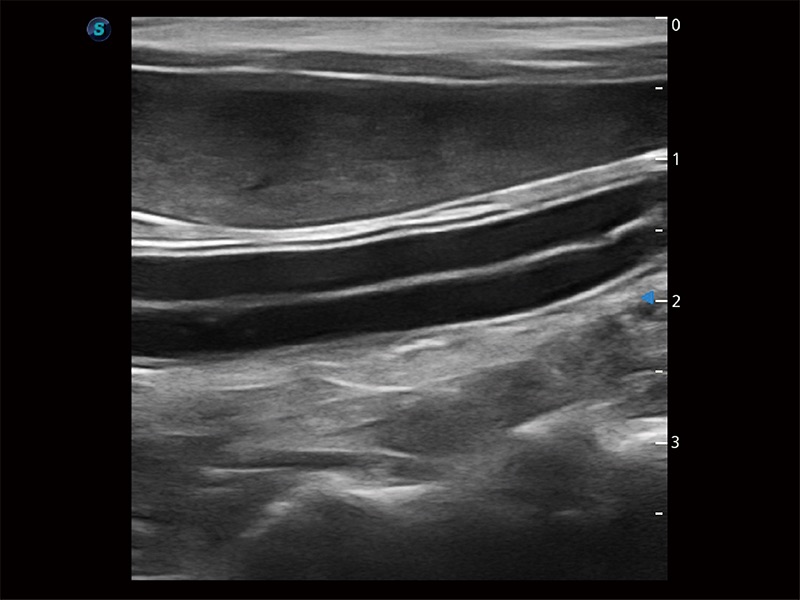

(犬)腸道

(貓)二尖瓣M型